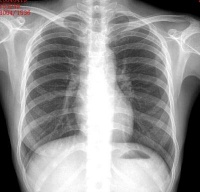

胸部正位平片

起源和发展  1895年德国的物理学家伦琴发现了X线,不久即被用于人体的疾病检查,并由此形成了放射诊断学。近30年来,CT、MRI、超声和核素显像设备在不断地改进核完善,检查技术核方法也在不断地创新,影像诊断已从单一依靠形态变化进行诊断发展成为集形态、功能、代谢改变为一体的综合诊断体系。与此同时,一些新的技术如心脏和脑的磁源成像和新的学科分支如分子影像学在不断涌现,影像诊断学的范畴仍在不断发展和扩大之中。